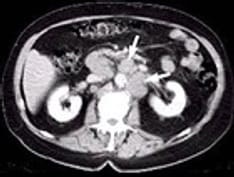

Axial computed tomography scan shows 2 rounded, mixed osteolytic-sclerotic lesions in the thoracic vertebral body of a 44-year-old woman with lung carcinoma.

-